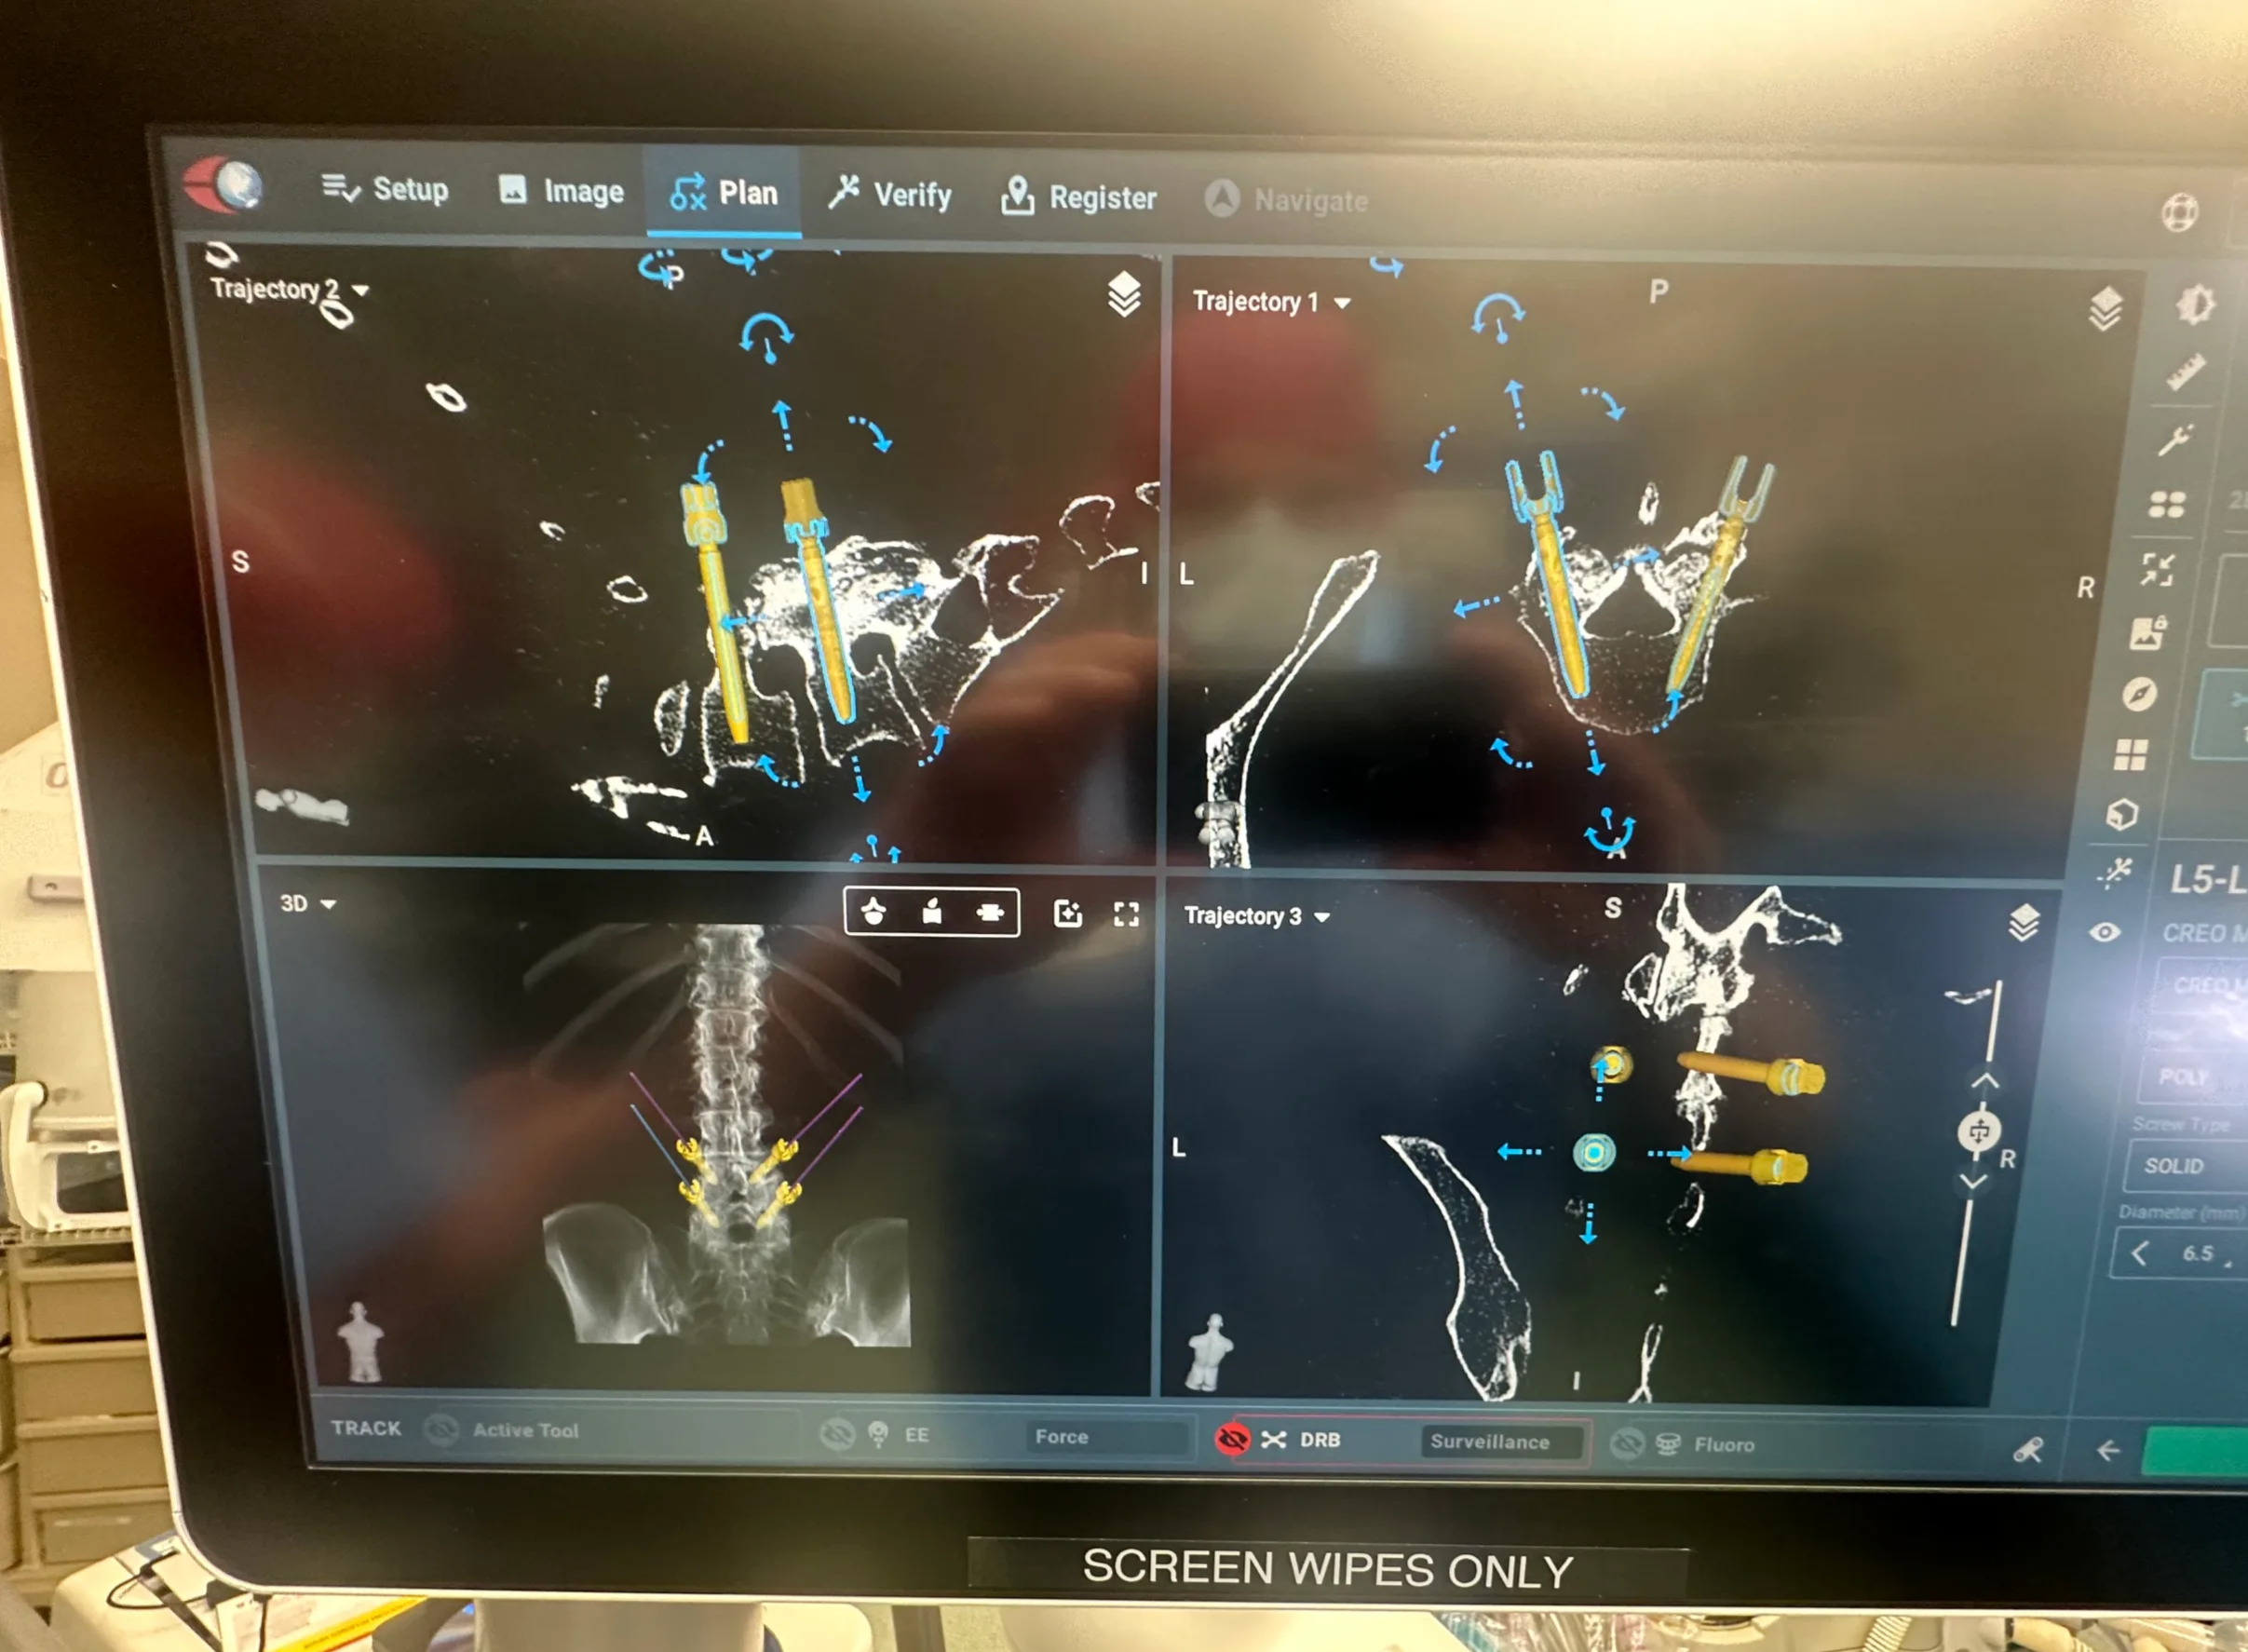

Lumbar disc replacement

Lumbar disc replacement

- TOPS Procedure with robotic guidance